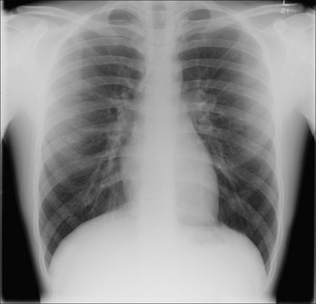

2. Pleuritic pain occurs.

image Pneumothorax and/or pneumomediastinum are recognised complications.

image

Figure 29.3 Acute asthma. Pleuritic chest pain. Left pneumothorax.